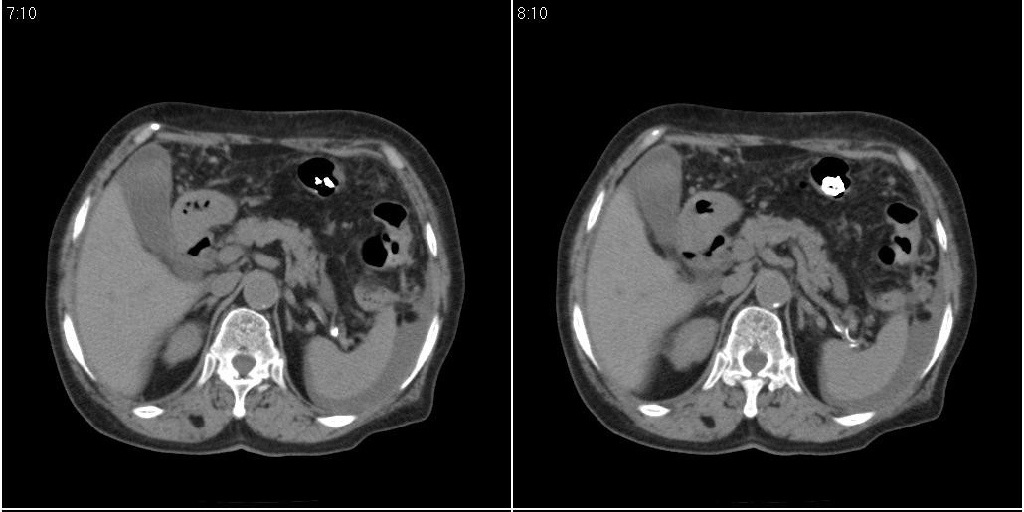

胆囊有问题么,是结石么?胆囊内异常密度平扫30hu左右,增强各期无变化。

支持!另腹腔少量积液。

胆囊内稍高密度影,无强化,胆囊壁增厚,周围见低密度影,右侧膈肌角及脾周水样密度,支持胆囊泥沙样结石,胆囊炎、胆囊窝积液,胸腹水。

1)胆囊炎,胆结石;胆囊新生物待排。2)胆囊窝积液。3)腹水。4)右侧少量胸腔积液。